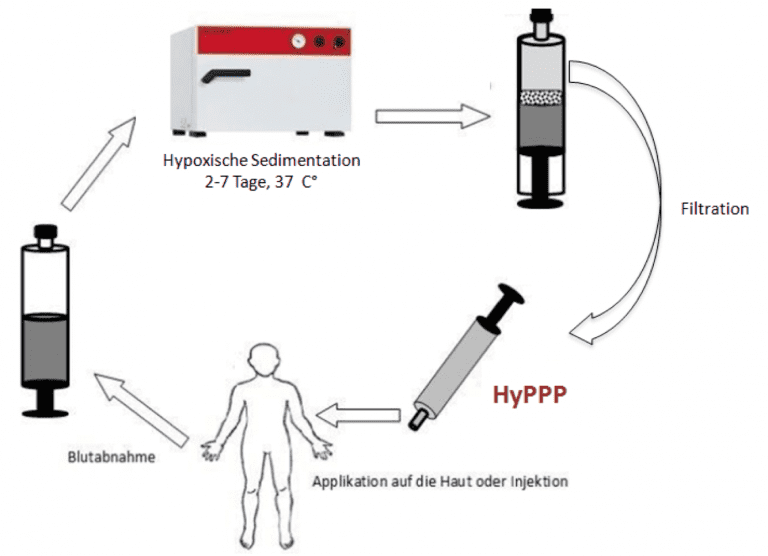

EmaCure®: Entwicklung eines personalisierten therapeutischen Ansatzes zur Wundheilung

Projektleiter: Dr. Philipp Moog

EmaCure® wird durch Konditionierung von peripheren Blutzellen unter wundsimulierenden physiologischen Bedingungen (Hypoxie, Temperatur) für einen definierten Zeitraum hergestellt. Dieser Ansatz stellt eine signifikante Verbesserung gegenüber den derzeit verfügbaren Systemen zur Herstellung von autologen, blutbasierten Zusammensetzungen, dar. Es ermöglicht eine Hypoxie induzierte Steigerung der Proteinkonzentration, im Vergleich zum Zeitpunkt der Blutentnahme.

EmaCure® kann in Form von Wundverbänden und injizierbaren Präparaten erfolgen, die vollständig zellfrei sind. Da die Proteinfaktoren aus dem autologen Blut des Patienten stammen, ist diese der therapeutische Ansatz patientenspezifisch. Unsere Forschungsbemühungen beschäftigen sich ebenfalls mit der Fähigkeit der generierten Sekretome auf unterschiedliche Gewebetypen.

Das EmaCure®-Konzept wird von einem multidisziplinären Forscherteam entwickelt, darunter Zellbiologen, Ingenieure, Kliniker und plastische Chirurgen sowie Spezialisten für translationale Therapien. Das Netzwerk der Kooperationsinstitute umfasst die TU München, die Hochschule München, die Fachhochschule München, sowie die Universitätsmedizin Göttingen.

Eine Patentanmeldung auf eines one-step device zur Vorbereitung und Bereitstellung der EmaCure®-Faktoren wurde erstmals im Februar 2012 eingereicht PCT/EP2013/051910;''Device based methods for localized delivery of cell-free carriers with stress-induced cellular factors''). Das Patent wurde im August 2013 veröffentlicht (IPN: WO 2013/113821 A1).